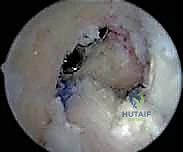

- الجراحة المجهرية وتنظير المفاصل بدقة 4K: يستخدم الدكتور هطيف أحدث تقنيات مناظير الركبة (Arthroscopy) المزودة بكاميرات عالية الدقة 4K، مما يتيح له رؤية أدق التفاصيل داخل المفصل، وتشخيص الأضرار المجهرية، وإجراء الجراحة بأقل تدخل جراحي ممكن (Minimally Invasive).

* التصوير بالرنين المغناطيسي (MRI): يوفر صورة مفصلة للأنسجة الرخوة. يحدد حالة الطعم المزروع سابقاً (هل هو ممزق، متآكل، أم سليم ولكنه غير فعال؟)، ويقيم حالة الغضاريف الهلالية والمفصلية.